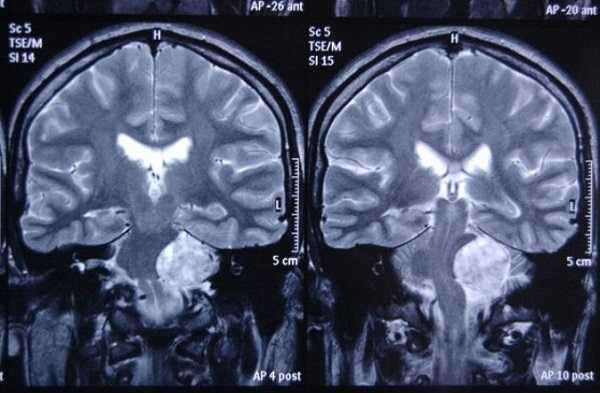

Типичные опухоли этой области невриномы (шванномы) и менингиомы. При невриномах может быть фрагмент опухоли во внутреннем слуховом проходе, что видно, особенно при МРТ головного мозга с контрастированием.

Вестибулокохлеарный нерв (VIII) состоит из 4 пучков. Опухоли происходят обычно из вестибулярной его части. Шваннома - инкапсулированная доброкачественная (градация 1) опухоль, происходящая из дифференцированных неопластических шванновских клеток оболочек периферических нервов. Невриномы ММУ составляют около 3% опухолей головного мозга. Часть шванном (двухсторонние слуховых нервов) связана с НФ 2 типа. Пик частоты между 40 и 60 годами. Растут медленно и крайне редко малигнизируются. Клинические проявления связаны с нарушением функции нерва и компрессией ствола. Шваннома может происходить из любого отрезка по ходу нерва и хорошо прослеживается при МРТ области ММУ. Невринома видна как на Т2-взвешенных, так и на Т1-взвешенных МРТ в виде округлого образования. Невриномы хорошо и равномерно усиливаются после МРТ с введением контрастного вещества. Невриномы области цистерны могут иметь компонент во внутреннем слуховом проходе, особенно, хорошо видимый при МРТ головного мозга с контрастированием. Изредка встречаются невриномы полностью расположенные внутри канальца. Они составляют наибольшую диагностическую сложность при МРТ, требуют тонких срезов и контрастирования. Менингиомы ММУ обычно типично расположены и при МРТ имеют характерную форму и типичные черты при МРТ с контрастированием. Однако редко встречаются внутриканальцевые менингиомы. При МРТ они неотличимы от неврином. Холестеатомы при МРТ имеют смешанную интенсивность сигнала, в зависимости от их содержимого. На диффузионно-взвешенных МРТ холестеатомы обычно яркие.

МР-сканирование при подозрении на менингиому мостомозжечкового угла, сагиттальная проекция

МР-сканирование головного мозга с прицельным изучением мосто-мозжечкового угла, фронтальный срез